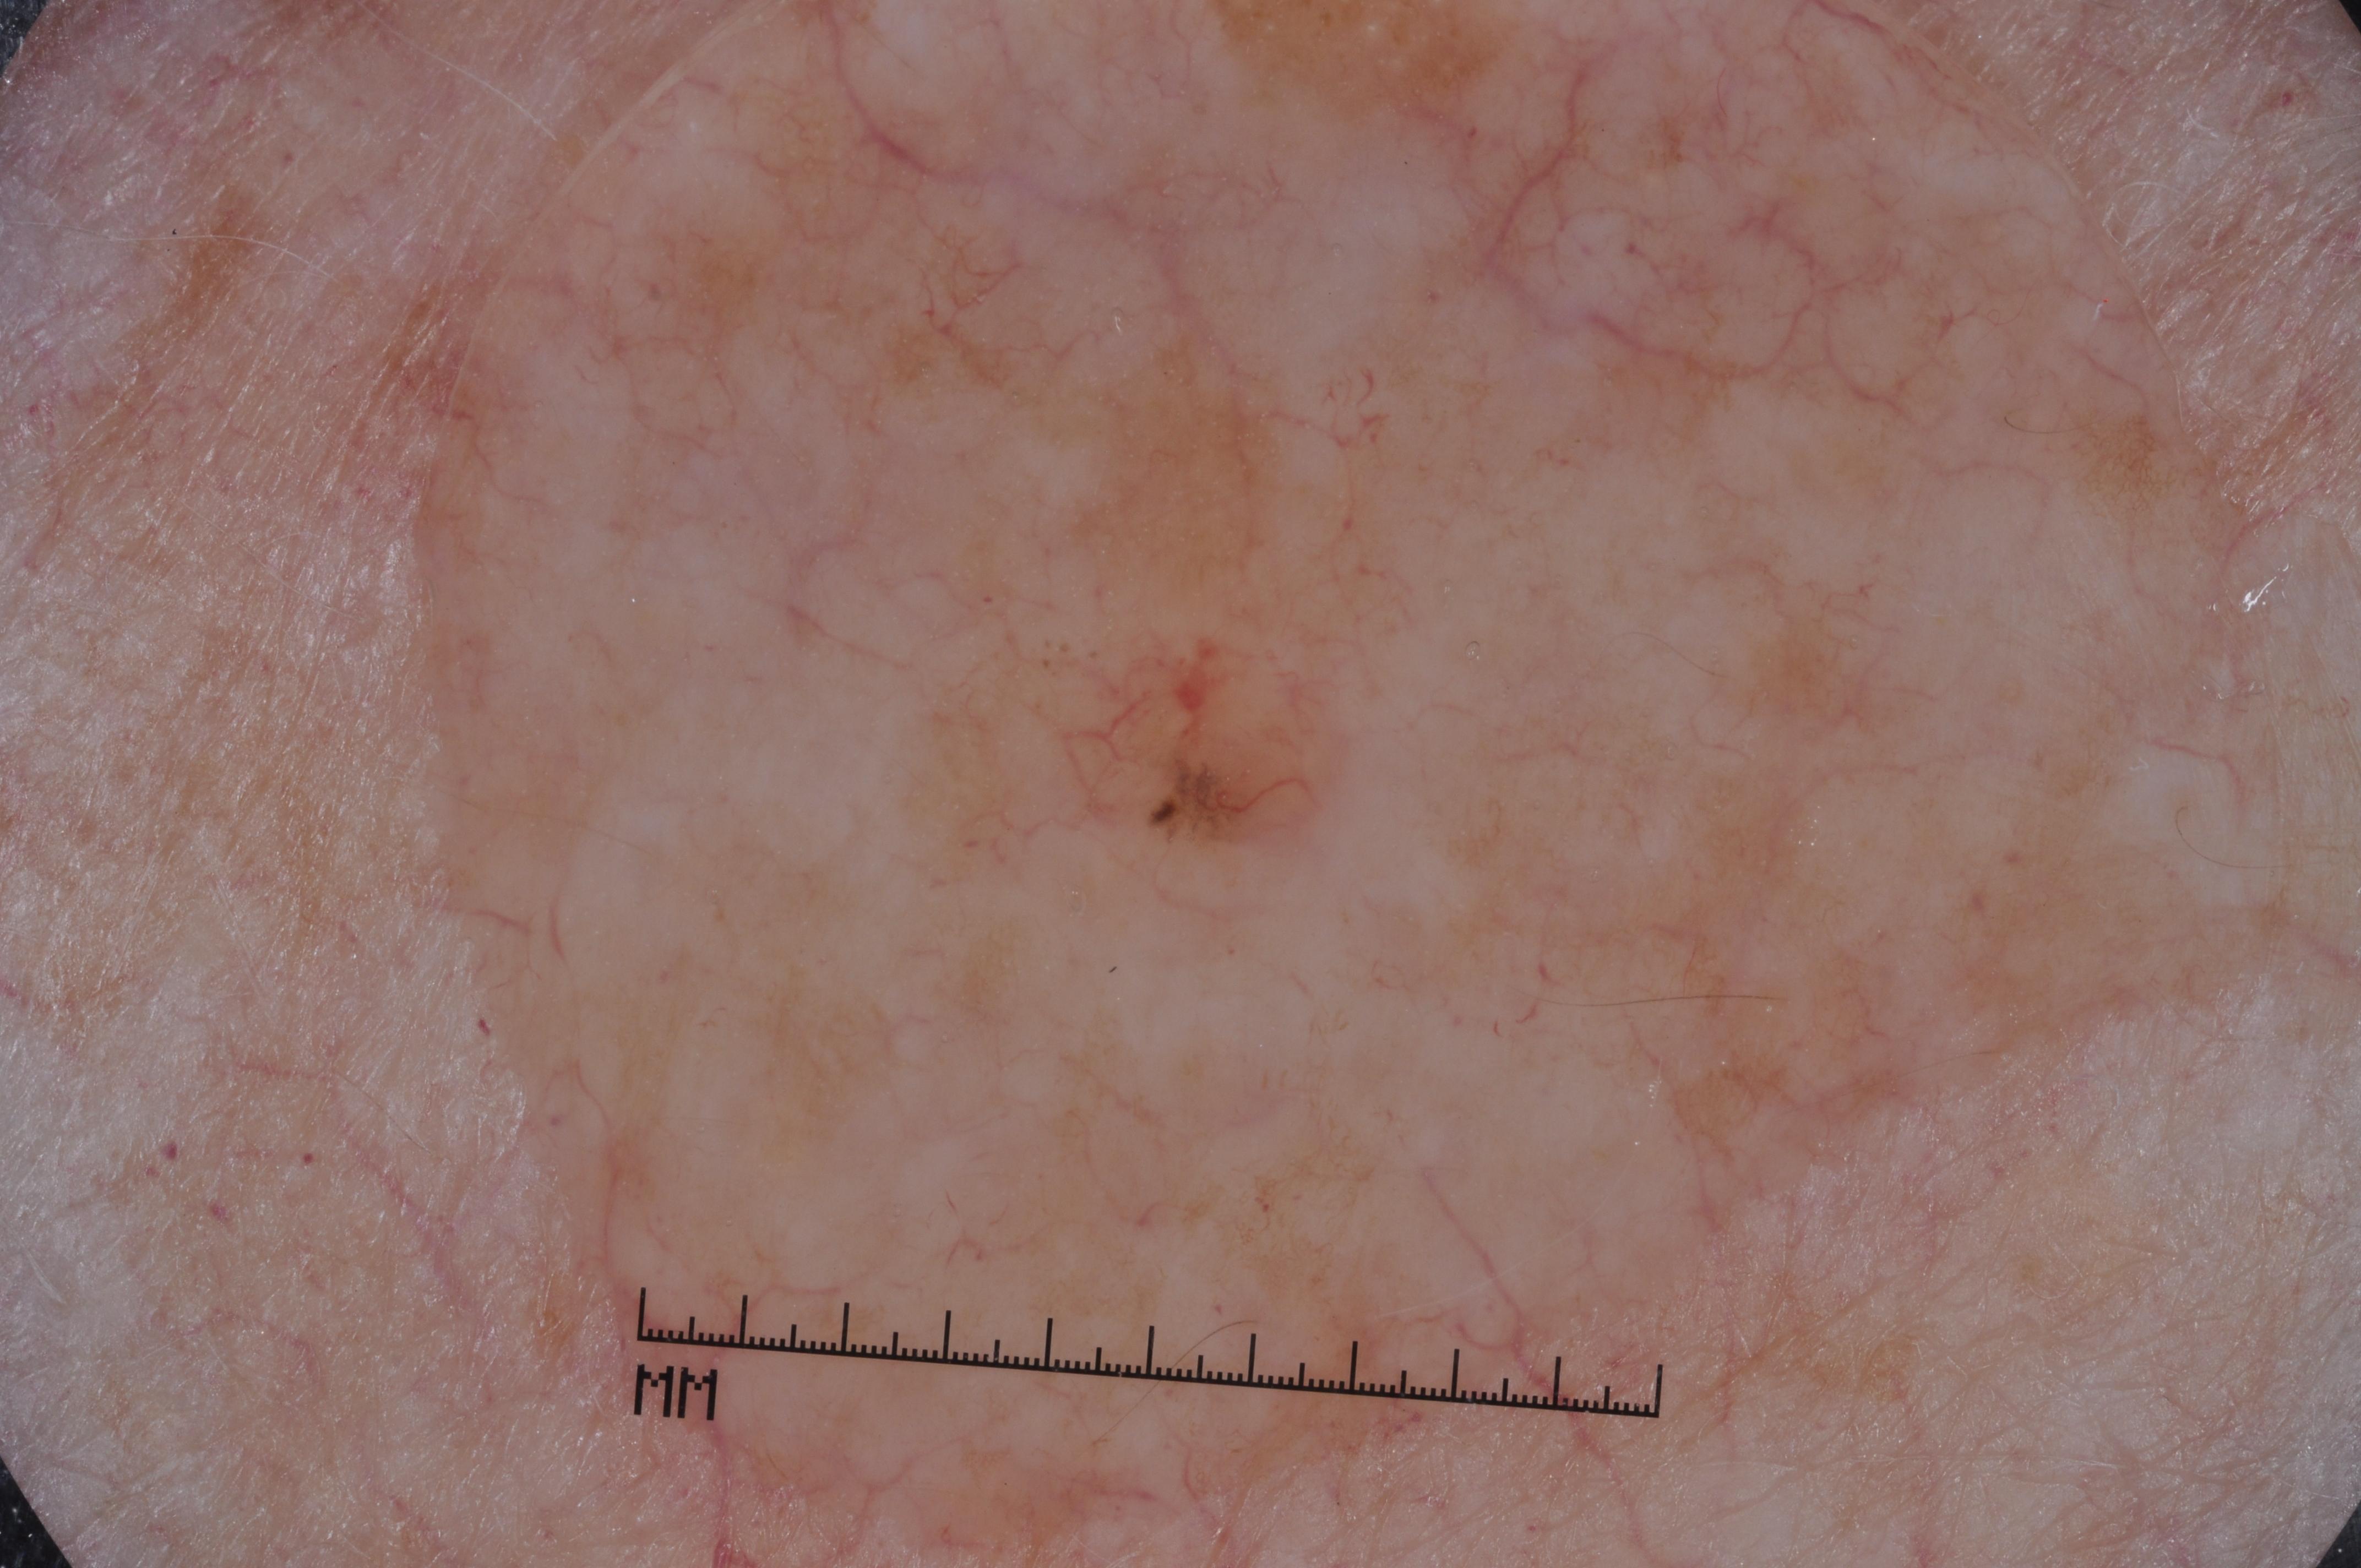

{

"age_approx": 70,

"anatom_site_general": "anterior torso",

"concomitant_biopsy": true,

"dermoscopic_type": "contact non-polarized",

"diagnosis_1": "Malignant",

"diagnosis_2": "Malignant melanocytic proliferations (Melanoma)",

"diagnosis_3": "Melanoma in situ",

"diagnosis_confirm_type": "histopathology",

"image_type": "dermoscopic",

"lesion_id": "IL_8276300",

"melanocytic": true,

"sex": "male"

}